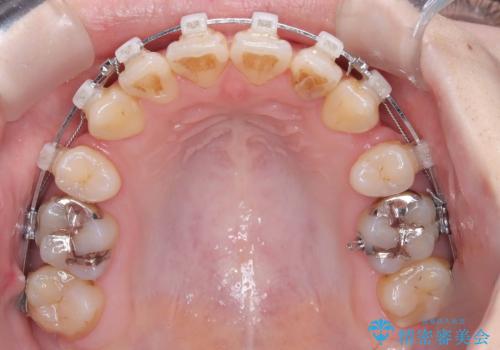

- ワイヤー矯正(クリア装置)

- 開咬と歯のデコボコ(叢生)、八重歯を主訴にご来院された患者様です。

矯正の精密検査の結果、上顎左右4番および下顎左右5番の計4本を抜歯し、ワイヤー矯正(クリア装置)にて治療を行いました。

開咬や歯列のデコボコが改善され、見た目だけでなく咬み合わせの機能面も大きく向上し、大変ご満足いただけました。

また、治療期間も比較的短期間で終了することができました。